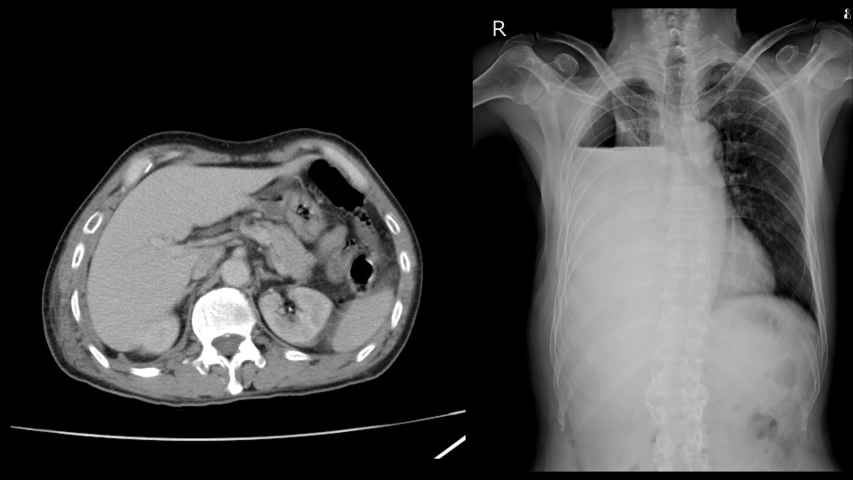

X 2 view

X 2 view 112 фотографий